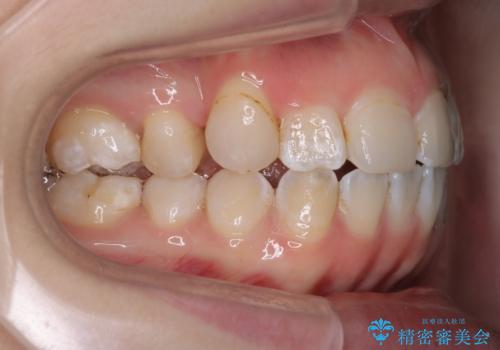

「フルリンガル矯正|アンカースクリューを活用し正中を整えた症例」

- 他院で矯正治療を受けていた患者様が、より理想的な仕上がりを求めて転院されました。主なお悩みは正中(前歯の中心)がズレていることで、歯並び全体をきれいに整えたいとのご希望でした。治療には舌側(裏側)に装置を装着するフルリンガル矯正を採用し、さらにアンカースクリューを用いて奥歯を後方へ移動(遠心移動)させることでスペースを確保し、正中を調整する計画を立てました。

矯正装置を装着し、アンカースクリューを活用しながら奥歯を少しずつ後ろへ動かし、正中を整えていきました。治療には時間がかかりましたが、計画通りに歯を移動させ、バランスの取れた歯並びへと仕上げることができました。裏側矯正のため、見た目を気にすることなく治療を進められた点も、患者様にとって大きなメリットでした。治療後は、「正中がしっかり合って、口元がスッキリした」とご満足いただきました。